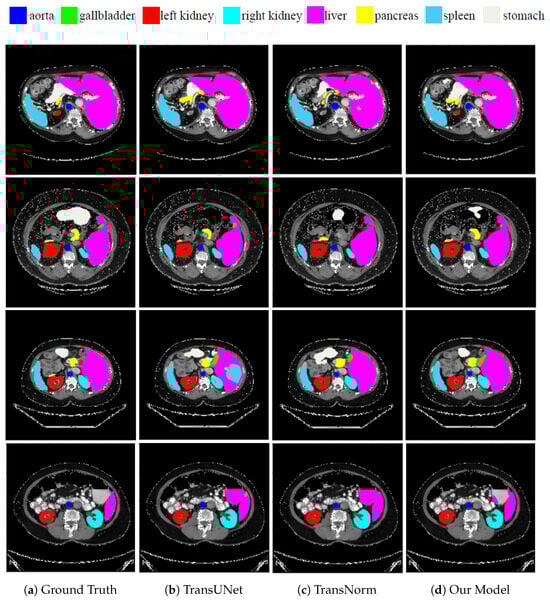

3.1. Synapse Multi-Organ Segmentation

| TransUNet [45,55] | 77.48 | 31.69 | 87.23 | 63.13 | 81.87 | 77.02 | 94.08 | 55.86 | 85.08 | 75.62 |

| TransNorm [42] | 78.40 | 30.25 | 86.23 | 65.10 | 82.18 | 78.63 | 94.22 | 55.34 | 89.50 | 76.01 |

| Proposed Method | 81.92 | 20.21 | 89.01 | 70.39 | 86.04 | 82.83 | 95.09 | 62.32 | 90.02 | 78.33 |